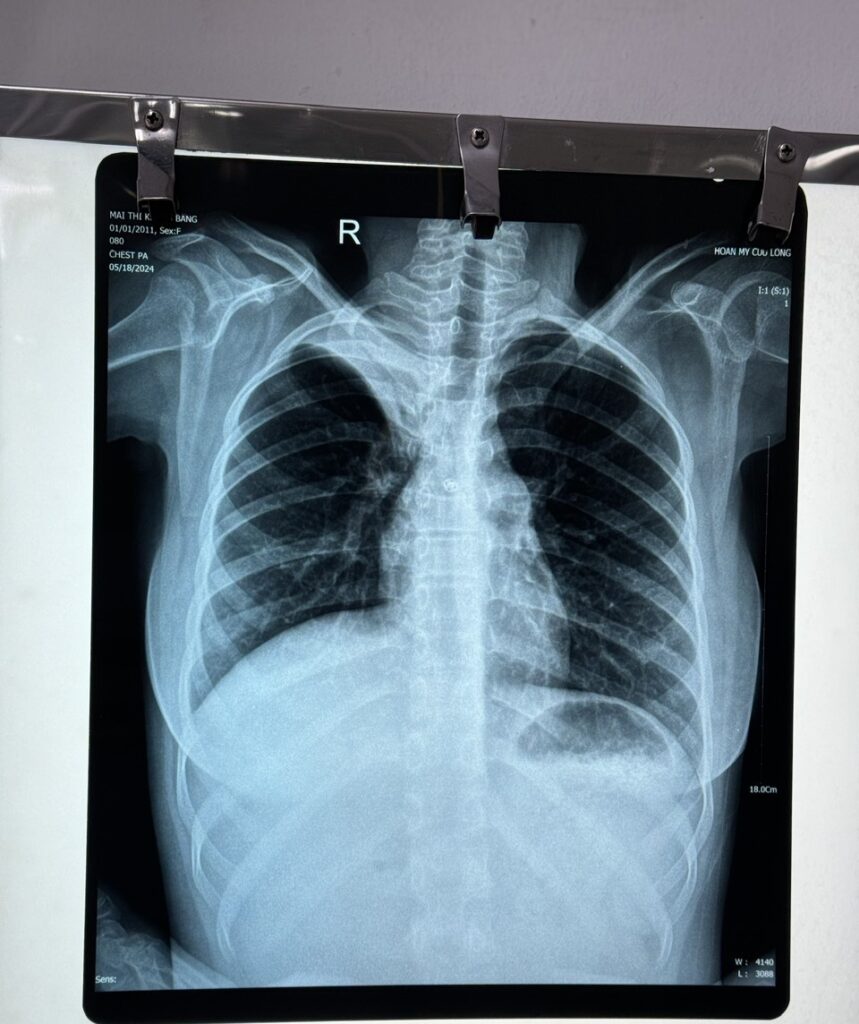

Sau khi thăm khám và thực hiện các cận lâm sàng cần thiết, kết quả X-quang phổi có hình ảnh đám mờ đồng nhất thùy trên phổi phải. Sau đó bé được chụp cắt lớp vi tính MSCT ngực ghi nhận kết quả: xẹp toàn bộ thùy trên phổi phải, kèm thâm nhiễm tạo đám mờ đồng nhất. Các xét nghiệm khác chưa ghi nhận bất thường. Bệnh nhi được chẩn đoán: viêm phổi thùy đỉnh phổi phải.

Hình X-quang trước (trái) và sau 06 ngày điều trị (phải)